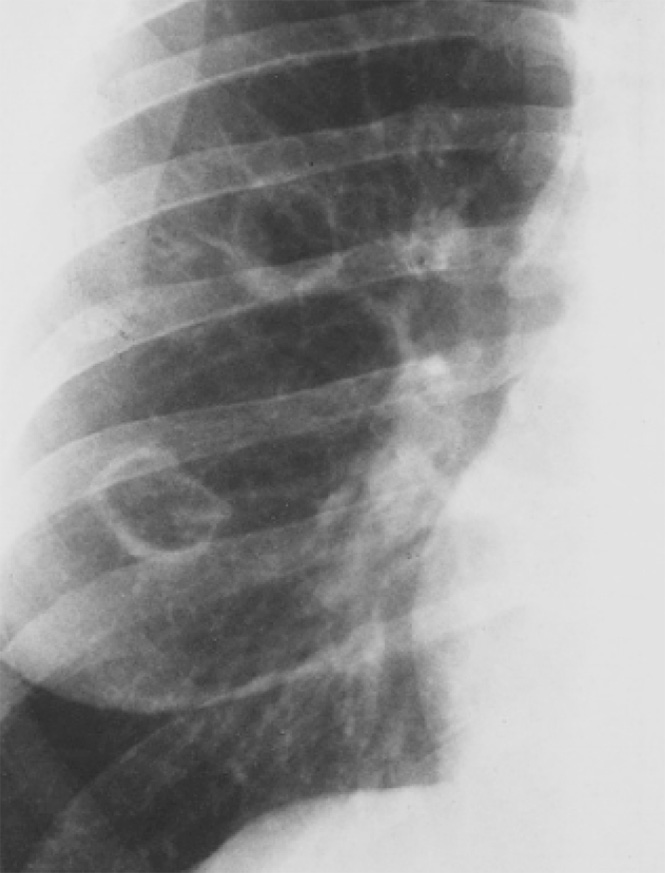

Рисунок 2. Гранулематоз Вегенера (увеличенный фрагмент рентгенограммы в прямой проекции – нижнее правое легочное поле). На фоне тени правого корня определяются 4 полостных образования в легком